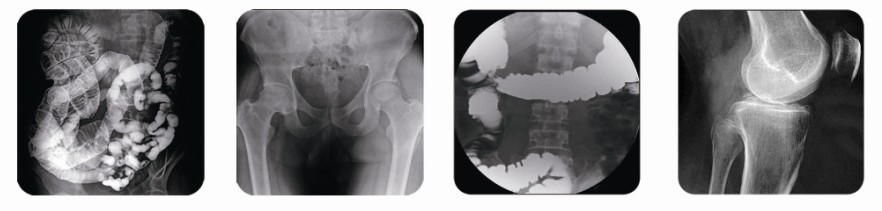

在國(guó)內(nèi)醫(yī)療器械行業(yè),普朗醫(yī)療也是比較出名的,尤其是胃腸造影機(jī)PLD6800,不僅能滿足臨床診斷需要,更能適應(yīng)醫(yī)院遠(yuǎn)期發(fā)展的需求,更好地為廣大患者服務(wù)。PLD6800胃腸造影機(jī)采用全球領(lǐng)先品牌原裝進(jìn)口加拿大CPI高頻主機(jī)和東芝高速球管,它與傳統(tǒng)的胃腸機(jī)相比有更加明顯的優(yōu)勢(shì)。最高逆變頻率可達(dá)200KHz,采用 0.6/1.2mm2雙焦點(diǎn)、300KHU大容量的高速X線管,適合長(zhǎng)時(shí)間高強(qiáng)度的臨床檢查。高清晰度的數(shù)字影像鏈,確保細(xì)微病灶也不會(huì)錯(cuò)過(guò)。如果您想了解詳情,可點(diǎn)擊圖片下方的紅色字體。有什么問(wèn)題可以具體咨詢頁(yè)面漂浮的在線客服人員。

(高頻數(shù)字化醫(yī)用診斷X射線機(jī)PLD6800控制臺(tái))